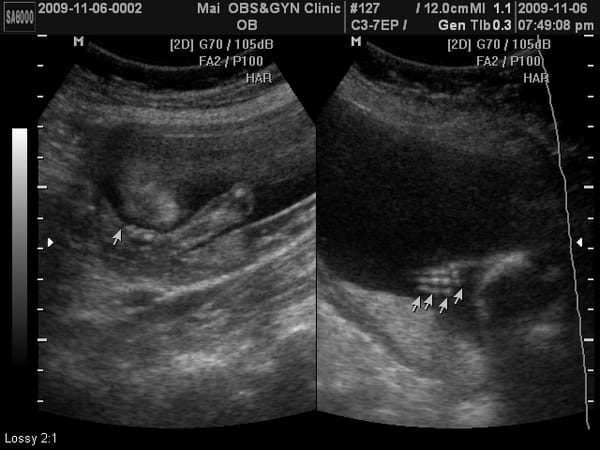

第三次產檢,驗尿ok,血壓ok,體重58。 (看來我這一胎應該會破70公斤) 抽了一根管的血去驗唐氏症,下回產檢聽報告。 醫生又再一次數了小老虎的手指頭給我們看。 上面那張照片左邊,似乎有看出臉型,是我的錯覺嗎? 她是趴著的。 傅說,跟她姐姐一樣愛趴著睡耶。 我是擔心她這樣趴著會不會沒氣。(烏鴉飛過。。。。) 產檢完之後,小老虎開始很喜歡胎動,特別是我吃泡菜的時候她會很興奮,媽媽我 […]…